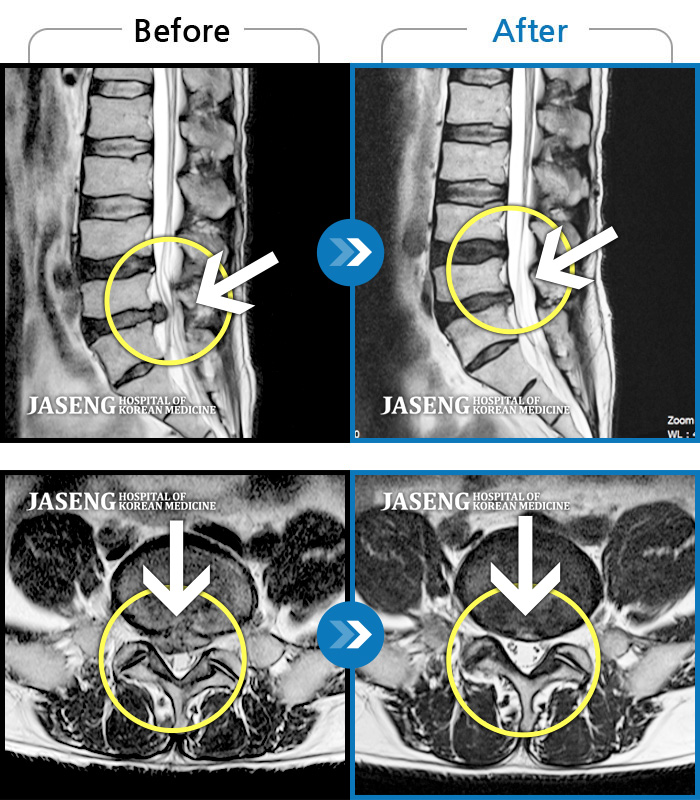

MRI 치료사례

좌측 엉치에서 발까지 당기는 통증